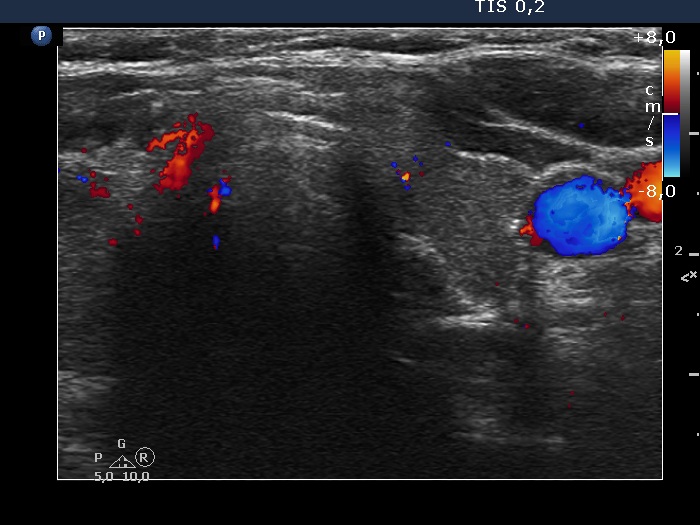

Right lobe, longitudinal scan

Left lobe, transverse scan, color Doppler mode. The vascularity is decreased.